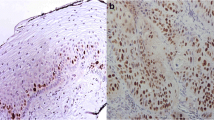

To identify DEPs, protein abundance data were processed to remove the proteins, which were quantified in less than 50% samples followed by imputation of missing values in the remaining, if any. In this way, 1343 proteins were sorted for statistical analysis (Supplementary File 1). To begin with, the volcano plot identified 201 DEPs with fold-change threshold 2 and t-test p-value threshold 0.05, of which 188 proteins were upregulated and 13 downregulated in cervical cancer tissues compared to controls (Fig. 3, Table 1, Supplementary File 2). The list of upregulated proteins included cofilin-1 (CFL1), DnaJ homolog subfamily C member 5 (DNAJC5), syntaxin-7 (STX7), tax1-binding protein 3 (TAX1BP3), PRA1 family protein 2 (PRAF2), syntenin-1 (SDCBP), integrin beta-5 (ITGB5), calponin-3 (CNN3), TPM4, catalase (CAT), malate dehydrogenase, mitochondrial (MDH2), transgelin-2 (TAGLN2), nucleoside diphosphate kinase A (NME1), HLA class I histocompatibility antigen (HLA), transferrin receptor protein 1 (TFRC), 14-3-3 protein beta/alpha (YWHAB), integrin alpha-V (ITGAV), peroxiredoxin-2 (PRDX2), tumor protein D52 (TPD52), glutathione synthetase (GSS), catenin alpha-1 (CTNNA1), RNA-binding protein FUS (FUS), prosaposin (PSAP), nucleobindin-1 (NUCB1), nucleobindin-2 (NUCB2), beta-2-microglobulin (B2M), stathmin (STMN1), tapasin (TAPBP), glucosamine-6-phosphate isomerase 1 (GNPDA1), proliferating cell nuclear antigen (PCNA), growth factor receptor-bound protein 2 (GRB2), tumor-associated calcium signal transducer 2 (TACSTD2), cadherin-1 (CDH1), and prohibitin (PHB). On the other hand, plasminogen (PLG), serum albumin (ALB), serotransferrin (TF), hemopexin (HPX), alpha-2-HS-glycoprotein (AHSG), AFM, apolipoprotein A-II (APOA2), and transmembrane protease serine 13 (TMPRSS13) were found downregulated in cervical cancer. For orthogonal validation, two of the DEPs, STMN1, and AFM were analyzed by western blotting. Similar to LC–MS/MS-based label-free quantitation, STMN1 was found upregulated, while AFM was downregulated in cervical cancer tissue samples (Fig. 3 inset).

Differentially expressed proteins (DEPs) selected by volcano plot analysis. Both fold-change (FC) and p-values were log-transformed. (Insert) Orthogonal validation of stathmin (Uniprot accession P16949) and afamin (Uniprot accession P43652) expression in cervical cancer and control tissue samples by western blotting. GAPDH was used as an internal control; C1 and C2: controls; P1 and P2: cervical cancer

The expression of two proteins, STMN1 and AFM was also validated by western blotting. STMN1, also known as oncoprotein 18 is a cytosolic phosphoprotein that plays an important role in microtubule dynamics that regulate mitosis and is essential for cell division and proliferation. Higher expression of STMN1 has been marked in cancer tissue samples of the ovary, endometrium, breast, and cervix (Curmi et al. 2000; Wei et al. 2008; Su et al. 2009Trovik et al. 2011). It is known to cause mitotic arrest enough to persuade tumorigenesis, tumor invasion, metastasis, and chemoresistance (Howitt et al. 2013). Associated with poor outcomes, overexpression of STMN1 in high-grade cervical cancer has been correlated with its involvement in the progression of disease with more aggressive behavior due to its oncogenic properties (Xi et al. 2009; Howitt et al. 2013). Thus, it can be explored further as a potential diagnostic marker as well as a therapeutic target for cervical cancer, specifically in high-grade malignancies. Other protein, AFM is a highly glycosylated member of the albumin gene family abundantly present in human plasma and other biological fluids (Dieplinger and Dieplinger 2015). It is a multi-functional vitamin E transporter that interacts with fatty-acylated Wnt proteins and helps them in retaining their biological activity during intracellular trafficking (Nusse and Varmus 2012; Wilson 2017). Wnt proteins are signaling molecules involved in the regulation of various cell development processes like proliferation, differentiation, migration, invasion, apoptosis, and tissue homeostasis (Wilson 2017). AFM expression has been reported in different cancers like gastric, bladder, colorectal, breast, and thyroid cancer and found significantly downregulated in ovarian cancer (Jackson et al. 2007; Dieplinger and Dieplinger 2015). A reduced expression of AFM in cervical cancer tissue samples correlates with previous reports of a negative correlation between AFM expression and cancer progression. However, not much information is available about the functional aspects of AFM. The targeted studies exploring the physiological role of this protein can uncover several unknown facets of cervical cancer pathogenesis, which can help us in designing improved therapeutics.